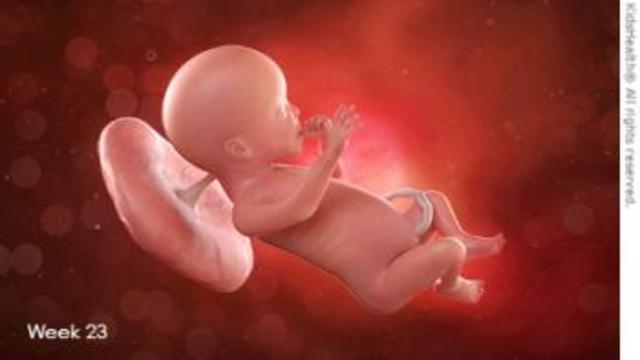

• Semana 23-25

Semana 23-25

La médula ósea comienza a producir glóbulos.

Se desarrollan las vías respiratorias inferiores de los pulmones del bebé.

El bebé empieza a almacenar grasa.